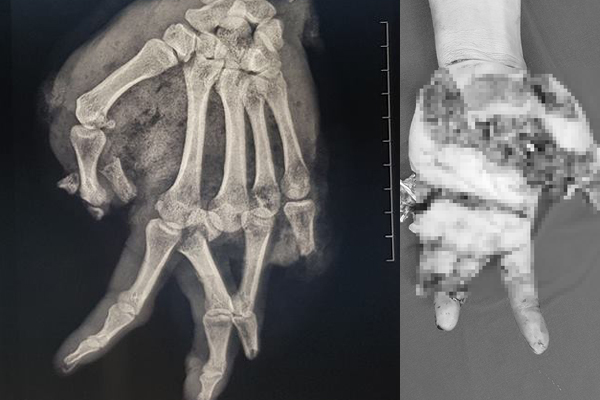

04/01/2019 15:32Ăn lẩu bằng bếp gas mini, nam thanh niên bị nổ nát bàn tay

BS Vũ Hữu Trung, Khoa Khoa Chấn thương Chi trên và Vi phẫu thuật, BV TƯ Quân đội 108 cho biết, khoa vừa tiếp nhận nam bệnh nhân ở Hà Nội bị bầm dập toàn bộ bàn tay do bình gas mini phát nổ.

Bệnh nhân cho biết, khoảng 20h ngày 2/1, trong lúc thay bình gas mới cho bếp gas mini để ăn lẩu, bình gas bất ngờ phát nổ, khiến bàn tay trái bệnh nhân bị dập nát nặng. Ngay lập tức, bệnh nhân được băng cầm máu vết thương và chuyển vào BV 108 cấp cứu.

BS Trung cho biét, bàn tay bệnh nhân bị tổn thương vết thương rất phức tạp, dập và lóc da gần như toàn bộ, ngón cái và ngón út dập nát hoàn toàn, ngón 4 gãy 2 đốt, ngón giữa gãy hở xương nền...

Bệnh nhân sau đó được xử trí cắt lọc vết thương, tạo mỏm cụt cho ngón út, ngón cái và ngón áp út; khâu da định hướng.

Bệnh nhân vẫn đang điều trị tại BV, sẽ tiếp tục được thay băng, chăm sóc vết thương; dự phòng và xử trí hoại tử thứ phát, sau đó từng bước làm liền vết thương.